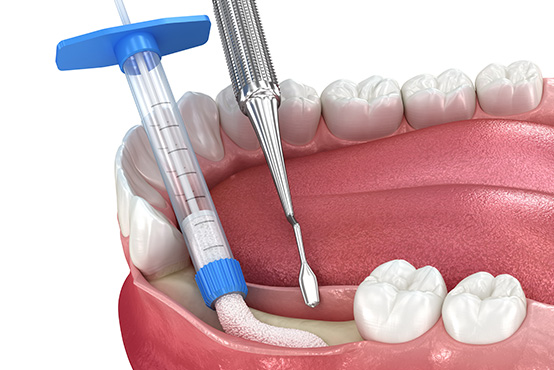

Dr. Linsky offers a comprehensive range of oral and facial surgical procedures, including dental implants, wisdom tooth removal, jaw surgery (orthognathic surgery), bone grafting, sinus lifts, TMJ treatment, and facial trauma care. Whether you’re seeking to restore missing teeth, correct jaw alignment, or relieve chronic pain, you can trust Dr. Linsky’s experience and precision. We combine advanced techniques with a personalized approach to help you achieve the healthiest, most functional, and most natural results possible.